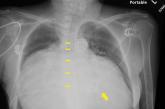

Enlarged cardiac silhouette on chest x-ray

Substantially enlarged cardiac silhouette